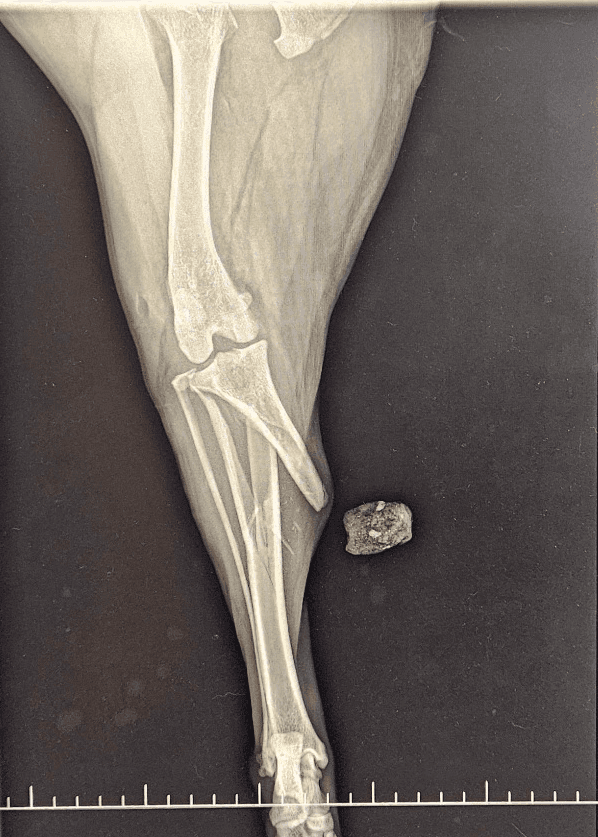

Radiographie Numérique

Une radiographie numérique de dernière génération et un capteur plan avec résolution pixel performante permettent de réaliser des clichés de grande qualité.

Leur interprétation est aidée par un logiciel d'intelligence artificielle.

C'est un outil diagnostique indispensable dans la recherche de multiples pathologies.